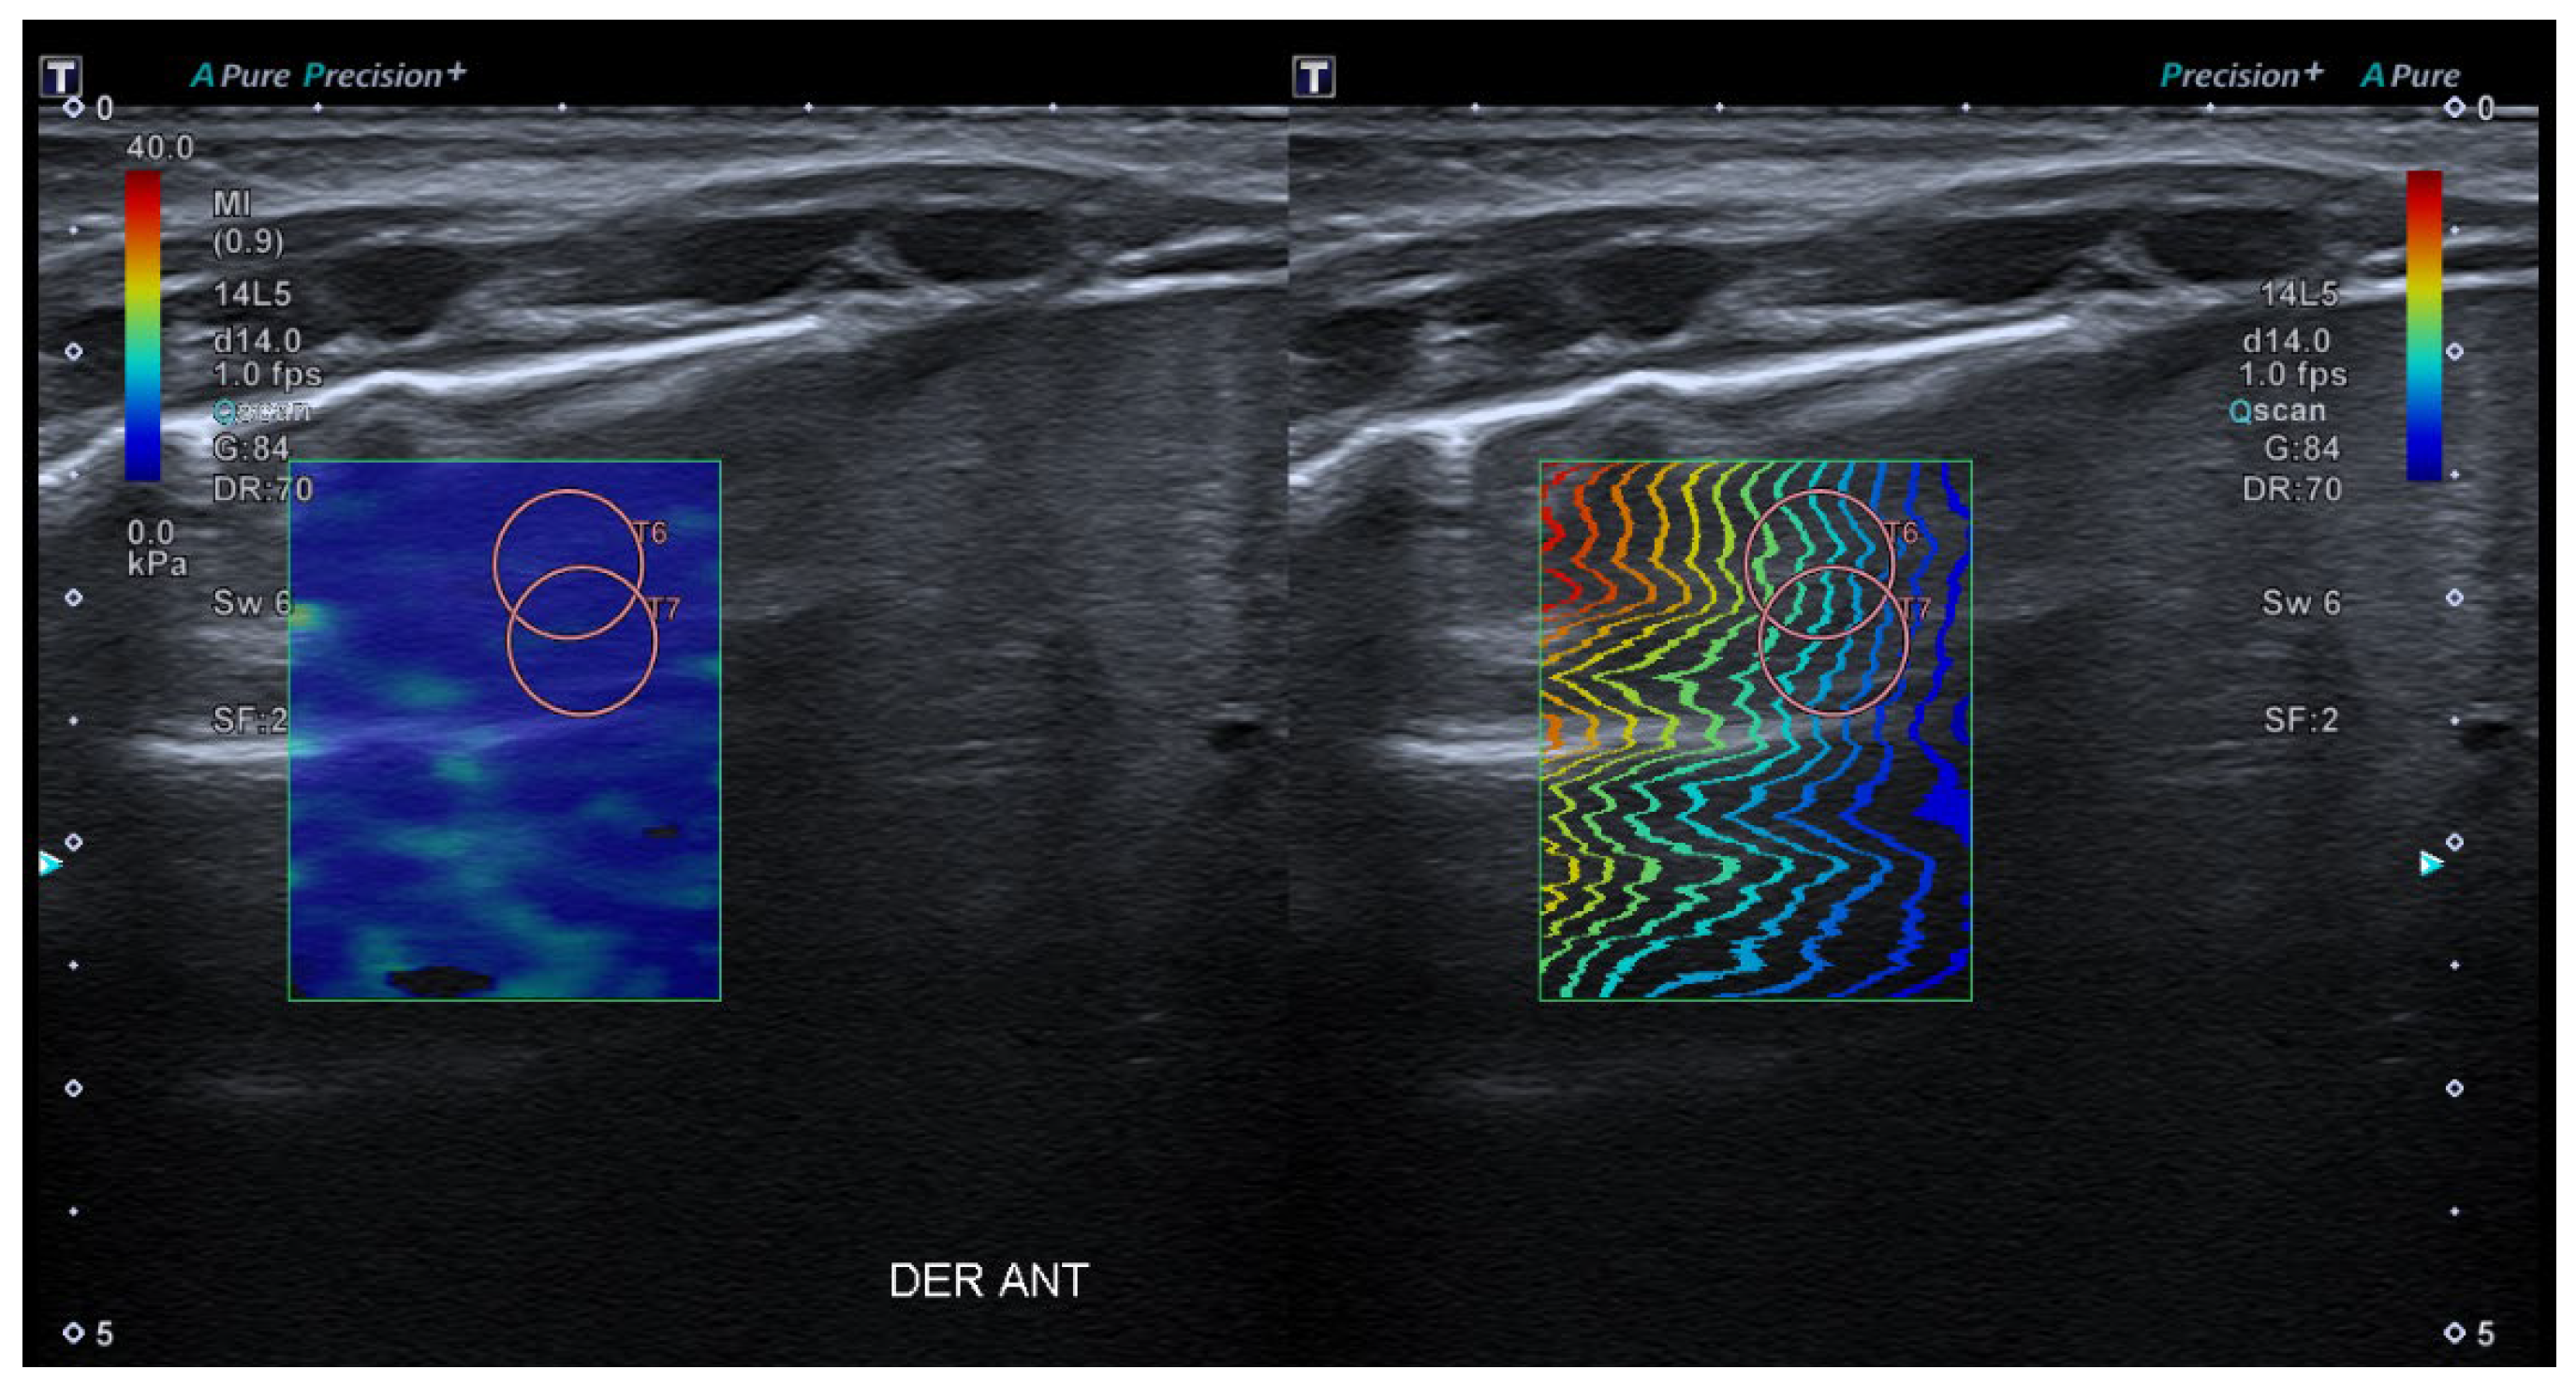

- 2D-Shear Wave Elastography (SWE): This is the latest and newest shear wave imaging technique. Like ARFI or pSWE, it uses acoustic radiation stimulation but, in this case, it rapidly scans multiple focal areas. This creates a virtual cylindrical shear wave cone that allows for the real-time monitoring of shear waves in 2D to measure their velocity, which is displayed on a quantitative colour map superimposed on a B-mode image (Figure 5). SWE has been extensively applied to characterize liver fibrosis [30,31], breast masses [32,33], prostate cancer lesions [34], thyroid nodules [35] and cervical lymph nodes [36]. In these contexts, SWE displayed low variability with respect to SE [37].